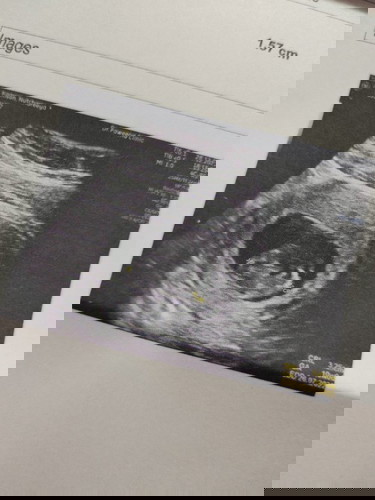

ใครทีมเดือนกรกฎาบ้างคะ ของเรา 10 สัปดาห์ 4 วัน เมื่อวานหมอนัดคุณหมอบอกว่าลูกเราแข็งแรงดีนอนน่ารักมาก

ท้องแรกดีใจมากเลยค่ะ

ทีมเดียวกันค่ะ ตอนซาว14วีคตอนนี้ได้15วีคเเล้วค่ะ หมอบอกน้องเเข็งเเรงดีค่ะ